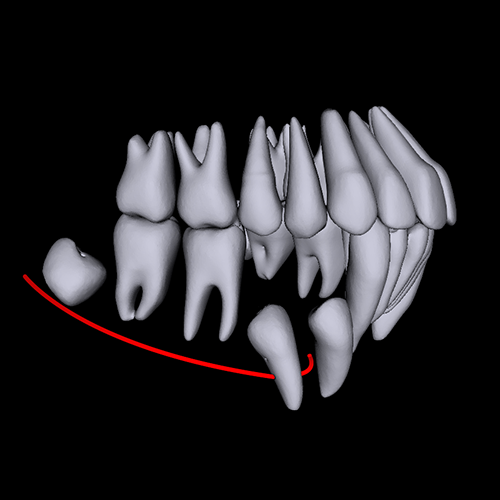

Get full 3D Segmentation analysis from any CBCT scans! Free 1 month unlimited uploads use code number A20011M by registration only at the link below: *You MUST enter the code number when you sign up for a paid program otherwise you will not receive the free month!! ORCA’s AI technology can receive any CBCT DICOM file and automatically generate full 3D segmentation. This helps you Increase your diagnostic confidence and improve Doctor - Patient communication. ORCA AI also offers automated 2D cephalometric analysis, with no human interaction. Just upload the CEPHX file to the cloud and in a few seconds you get full printed report! Free 1 month unlimited uploads use code number A20011M * by registration only at the link below: Https://cephx.com?aff=YD *You MUST enter the code number when you sign up for a paid program otherwise you will not receive the free month!! By using this code you will get Unlimited access to ORCA's cloud service. Unlimited number of uploads - CEPHX & CBCT. Easy toll to evaluate the patient case- anatomy, roots position and resorption detection, nerve canal anomalies and more. Plan implant and crown position in less than a minute. Share instantly with your patient or technician.